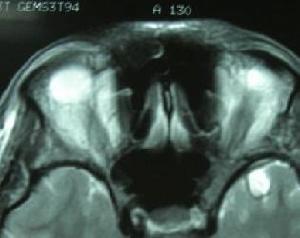

1986年DragerBehram同時報導了一組SDS的MRI表現。發現這些患者的殼核均呈短T2信號。以後Mario等認為殼核短T2信號對SDS的診斷具有診斷價值但對於成因觀點不一有作者認為源自一種順磁性物質——鐵元素,即可能與在此部位過度沉積的鐵有關細胞內鐵過多可加速去相位過程,縮短T2值在MRIT2加權像呈低信號。鐵元素沉積於殼核治療: